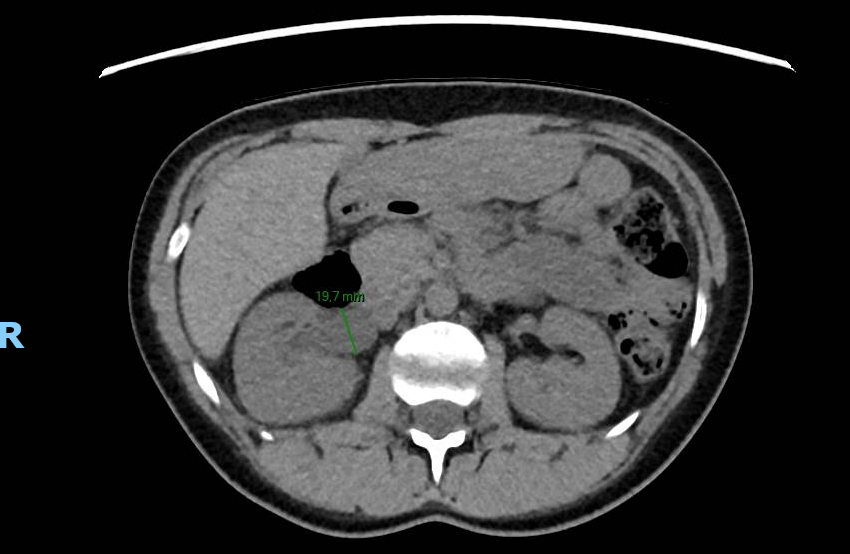

Le CT-scanner réalisé devant une colique néphrétique montre une compression urétérale droite extrinsèque sur une cup menstruelle. Cette dernière est retirée améliorant rapidement les douleurs.

Il existe 5 cas similaires publiés entre 2018 et 2020 (1), tous concernant l’uretère droit. Une étude ex-vivo comparant 14 marques de cup, de tailles et formes différents, a démontré qu’une cup trop grande ou trop rigide pouvait être la cause d’une compression des voies urinaires, en plus d’un inconfort (2).

Ce cas et la littérature qui y est liée démontre l’importance d’exclure la présence d’une cup en cas de colique néphrétique chez les femmes pré-ménopausées.